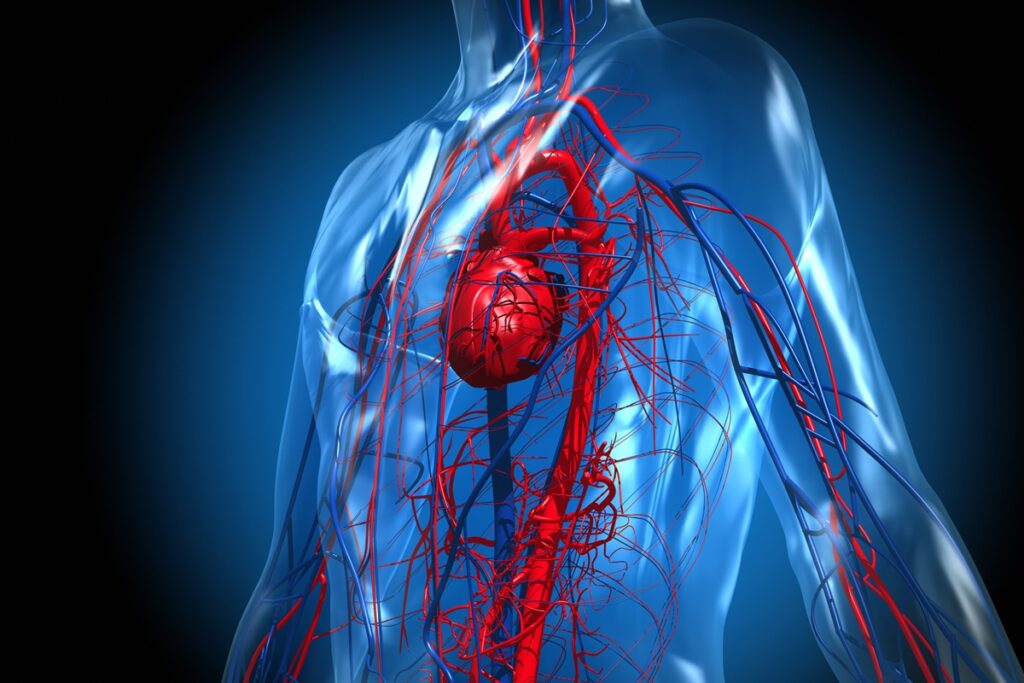

As férias e festas de fim de ano costumam ser “regadas” a doses de álcool, o que pode ser um problema para o bom funcionamento das artérias, veias e vasos linfáticos. Manter essas estruturas saudáveis é essencial para prevenir o surgimento de problemas de saúde, como trombose, infarto e acidente vascular cerebral (AVC).

Em entrevista à coluna Claudia Meireles, o neurocirurgião vascular Victor Hugo Espíndola enfatizou que algumas bebidas prejudicam a saúde vascular, aumentando a possibilidade da ocorrência de problemas.

Especialista em aneurisma cerebral, AVC e doenças vasculares no cérebro, o médico argumenta que bebidas alcoólicas açucaradas — como drinques, coquetéis e energéticos com álcool — são particularmente perigosas do ponto de vista vascular.

O neurocirurgião esclarece os impactos no corpo causados por essas opções:

- Combinação de álcool + alta carga glicêmica: piora a inflamação endotelial;

- Aumentam a resistência à insulina, a obesidade abdominal e a dislipidemia;

- Energéticos mascaram a sedação do álcool, favorecendo o consumo excessivo sem percepção;

- Maior impacto negativo sobre aterosclerose carotídea e cerebral.

De acordo com o médico, as bebidas alcoólicas açucaradas são as piores escolhas em termos metabólicos vasculares. “Os drinques com alto teor de açúcar têm pior perfil metabólico e inflamatório”, comenta.

Para pessoas que já tiveram AVC e outras doenças do sistema vascular, Victor Hugo reforça que não existe bebida alcoólica ‘segura’. “A prevenção passa pela redução significativa ou abstinência, especialmente para pacientes com fatores de risco prévios, como hipertensão, diabetes, fibrilação atrial, estenose carotídea e AVC prévio”, afirma o especialista.